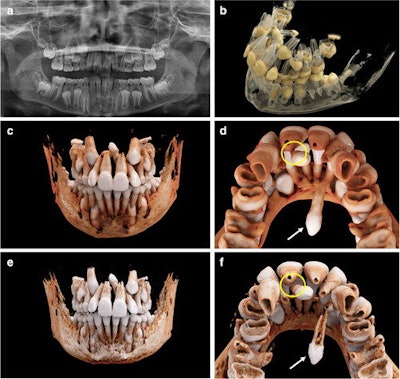

An 11-year-old boy with a mesiodens and a supplementary tooth (white arrows) within the hard palate. (a) An x-ray of the boy's mouth. (b) A display of the semitransparent reconstruction parameters. (c and d) The bone reconstruction parameters with a soft kernel can lead to artifacts in regions with teeth near each other (yellow circle in d, e, and f.) The same situation is shown with a hard kernel, allowing better differentiation between the roots of the mesiodens and of tooth #21 (yellow circle in f).The researchers noted that the current reconstruction time of up to 24 hours is not reasonable for routine clinical applications. However, as the software undergoes updates, reconstruction time is expected to significantly decrease, they wrote.